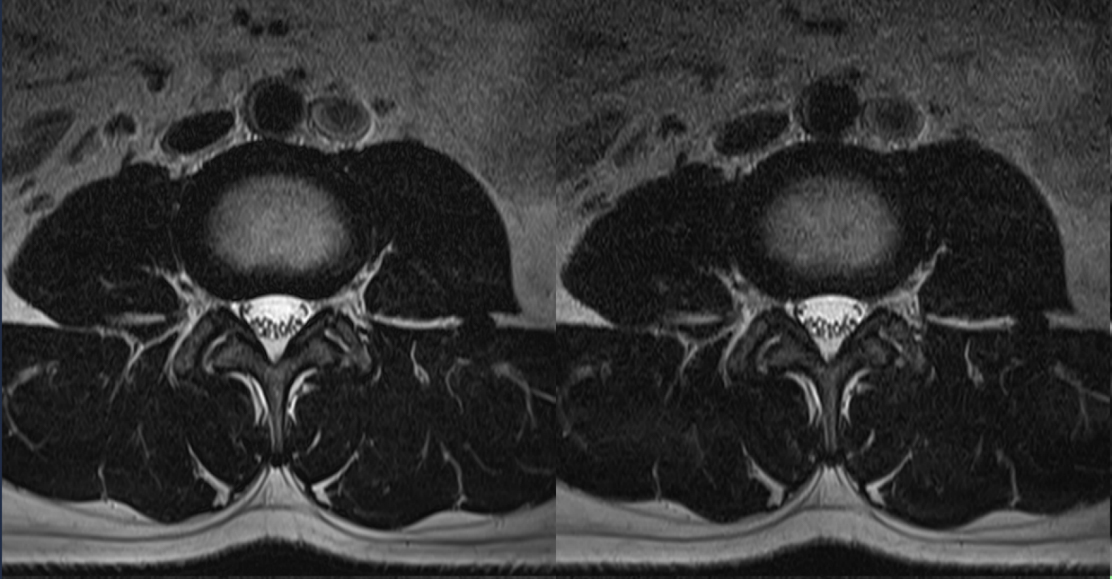

Original

Compressed SPEEDER 2.0

Compressed SPEEDER 2.5

Исходный и сжатый SPEEDER 2.0 и сжатый SPEEDER 2.5

Время сканирования 3:10

Vantage Orian 1.5T

Время сканирования 1:46

Время сканирования 1:18